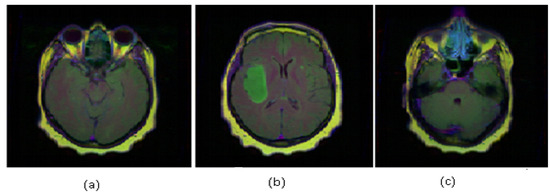

2.6. Data Set Description

| Dataset | No. of Instances | Image Format | Image Size | Classes | Sample Type | No. of Attribute | Attributes after PCA |

|---|---|---|---|---|---|---|---|

| Alzheimer’s | 100 | BMP | 2 | T2-weighted | 1296 | 39 | |

| Hemorrhage | 200 | JPEG | 2 | T1-weighted | 1296 | 70 |